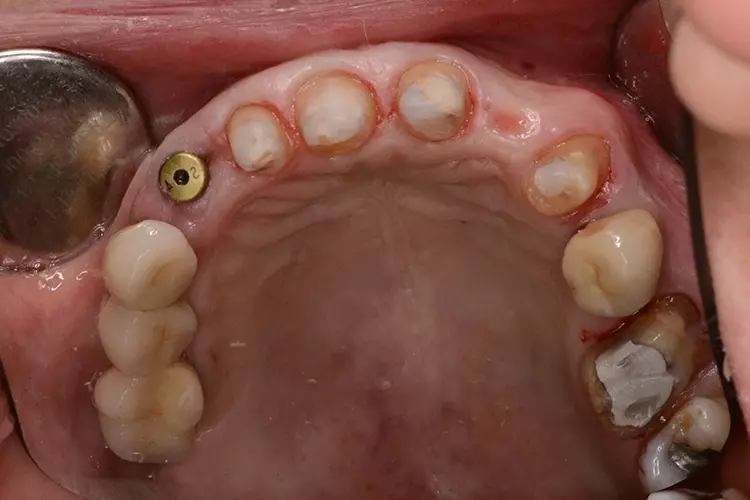

Neuversorgung Oberkieferfront auf Altimplantat 21

Die 49-jährige Patientin beklagte die ungleiche Höhe der Schneidekanten an den Kronen 11 und 21. In diesem Zusammenhang wurde das Gesamterscheinungsbild analysiert und entschieden, die Zähne 13-23 zu überkronen und dabei die Altkronen an 11 und an dem Implantat 21 zu erneuern. Die verschachtelt stehenden Zähne im Unterkiefer sollen im Nachgang per Aligner-Therapie ausgerichtet werden.

Dabei wurde die beabsichtigte Situation im Vorab per Wax-up simuliert. Beim Entfernen der Altkrone 21 wurde ersichtlich, dass ein Titanabutment eingesetzt wurde, an dem sich Konkremente und Zementreste befanden, die zu einer marginalen Mukositis am Implantat führten.